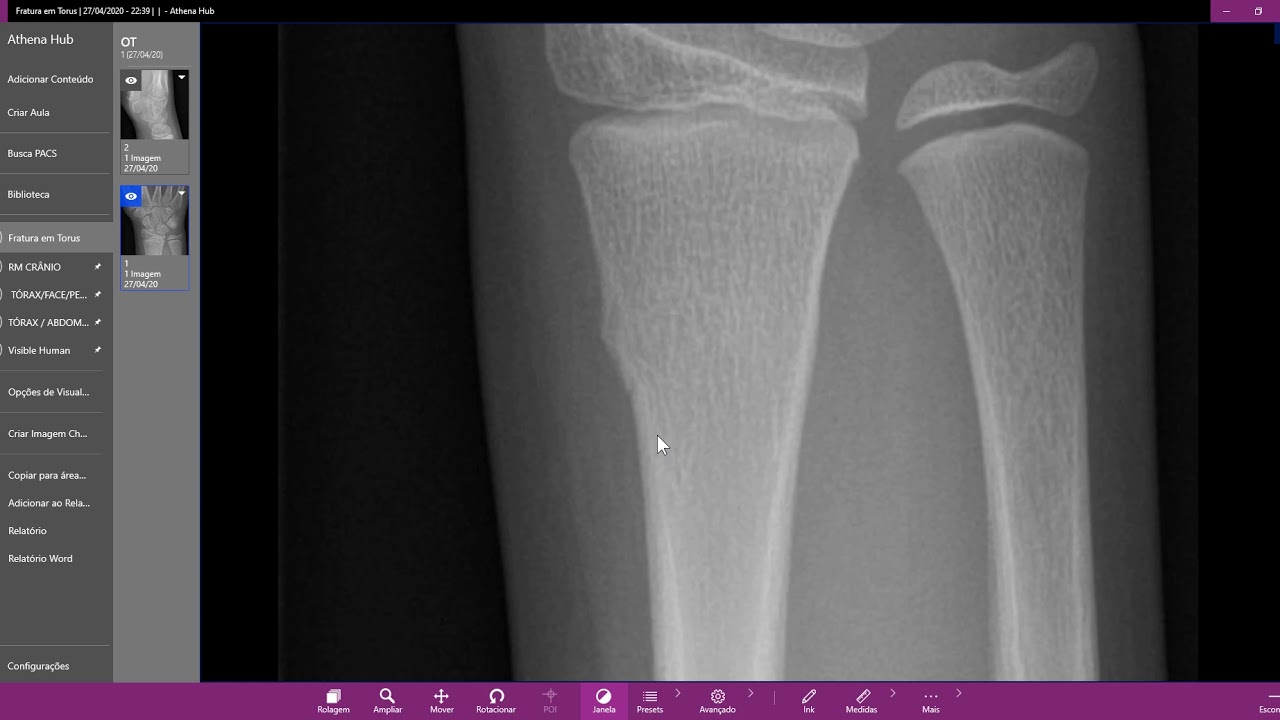

FRACTURA DE TORUS Fractura por compresión. A Torus fracture also known as a buckle fracture is the most common fracture in children. Ao invés de se romper de um lado a outro o que se observa é um amassado no osso. La fractura en rodete o torus. The position of the wrist in cast is usually slight flexion and ulnar deviation.

Existe uma deformação óssea sem traço aparente de fratura Torus Ocorre como uma fratura incompleta compressão em zona de transição de densidade óssea. Coleção sanguínea subperióstea de consistência elástica à palpação bem delimitada não ultrapassando a sutura óssea. FRATURA DE TORUS. É necessário uso de calha gessada. Redução incruenta gesso Redução incruenta fio de K instáveis cotovelo flutuante edema excessivo Redução cruenta fio de k Evitar passar o fio de k por dentro da fise.

FRATURA DE TORUS. Existe uma deformação óssea sem traço aparente de fratura Torus Ocorre como uma fratura incompleta compressão em zona de transição de densidade óssea. São fraturas muito comuns no punho. É uma lesão com excelente prognóstico na qual ocorre uma impacção diáfise na metáfise. Fratura de Tórus.

Incomplete fracture with cortical breach of only one side of the bone. A compressão ao longo do osso impacta o osso metafisario zona de maior porosidade e abaula a sua cortical. The word torus is derived from the Latin word Tori meaning. Occur in tandem with angulation. Fratura bem definida com mínima ou nenhuma formação de calo ósseo esclerose da cavidade medular e extremidades da fratura estreitadas e escleróticas.

Quando exacerbada essa formação calosa é chamada de pata de elefante. Fracturas toro também são comuns em pessoas com osteoporose devido à finura dos ossos. Se nos adultos as lesões nos músculos e tendões são mais comuns nas crianças as avulsões. It is a common occurrence following a fall as the wrist absorbs most of the impact and compresses the bony cortex on one side and remains intact on the other creating a bulging effect. A fratura ao invés de se romper de um lado a.